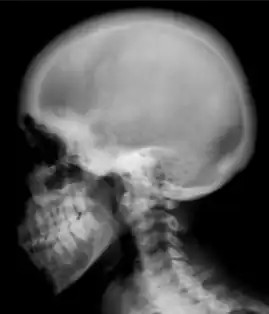

Renal osteodystrophy is usually diagnosed after treatment for end-stage kidney disease begins; however the CKD-MBD starts early in the course of CKD.[1][6] In advanced stages, blood tests will indicate decreased calcium and calcitriol (vitamin D) and increased phosphate, and parathyroid hormone levels. In earlier stages, serum calcium, phosphate levels are normal at the expense of high parathyroid hormone and fibroblast growth factor-23 levels. X-rays will also show bone features of renal osteodystrophy (subperiostic bone resorption, chondrocalcinosis at the knees and pubic symphysis, osteopenia and bone fractures) but may be difficult to differentiate from other conditions. Since the diagnosis of these bone abnormalities cannot be obtained correctly by current clinical, biochemical, and imaging methods (including measurement of bone-mineral density), bone biopsy has been, and still remains, the gold standard analysis for assessing the exact type of renal osteodystrophy.[6][15]

Ground glass density of the skull.[17] -